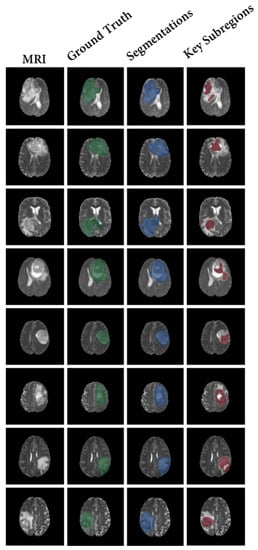

In contrast, the proposed CSF demonstrates the search process of key subregions, as shown in Figure 7. After training the segmentation results of our model using the proposed strategy, the segmented subregions are reduced to the key subregions.

Figure 7. The results of our framework (CSF). This result shows the decision-making process of the model, that is, how the model shrinks to key subregions. Specifically, the first column shows the T2 fluid attenuated inversion recovery (FLAIR) MRI. Columns 2–4 show the ground truth of tumor segmentation (Green), the segmentation results of the model (Blue), and the shrinkage results of the model (Red), respectively.